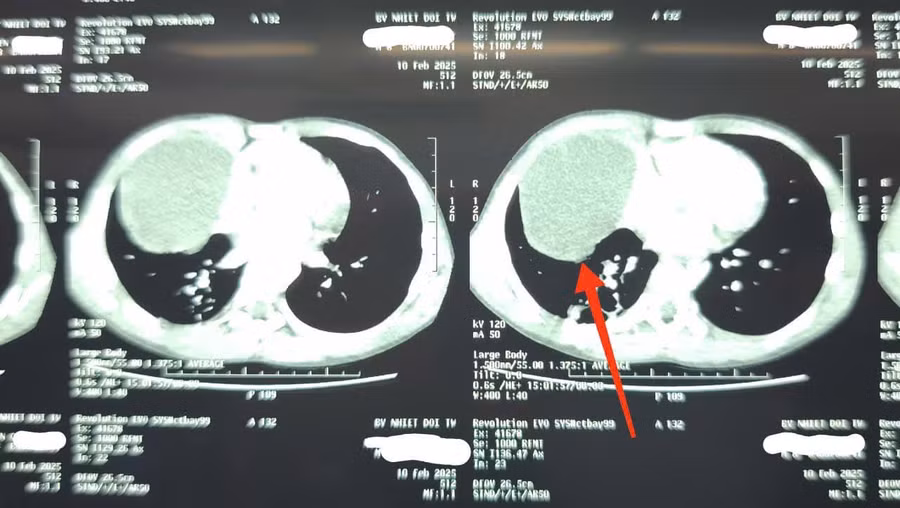

Tại khoa Nhi, hình ảnh X-quang cho thấy trắng xóa 1/2 dưới vùng ngực phải, siêu âm có tràn dịch màng phổi và có hình ảnh của nang dịch. Chụp cắt lớp vi tính phát hiện xẹp phổi dạng dải thùy dưới phổi phải, có nang dịch trung thất trước kích thước 72x80mm.

Bác sĩ Nguyễn Thành Lê, Phó Trưởng Khoa Nhi, Bệnh viện Bệnh Nhiệt đới Trung ương cho biết: "Thực tế, khối u nang dịch trung thất đã tồn tại từ trước nhưng chưa có triệu chứng. Cú ngã chỉ là sự trùng hợp về thời gian khi khối u nang bì vỡ, khiến triệu chứng trở nên rõ ràng hơn".

Các bác sĩ đã hội chẩn và chẩn đoán, bệnh nhi có một khối u nang bì - bệnh lý bẩm sinh hiếm gặp, trong lồng ngực. Đây là một dạng u hiếm gặp, có thể là lành tính hoặc ác tính, hình thành do sự di chuyển bất thường của tế bào mầm trong quá trình phát triển phôi thai.